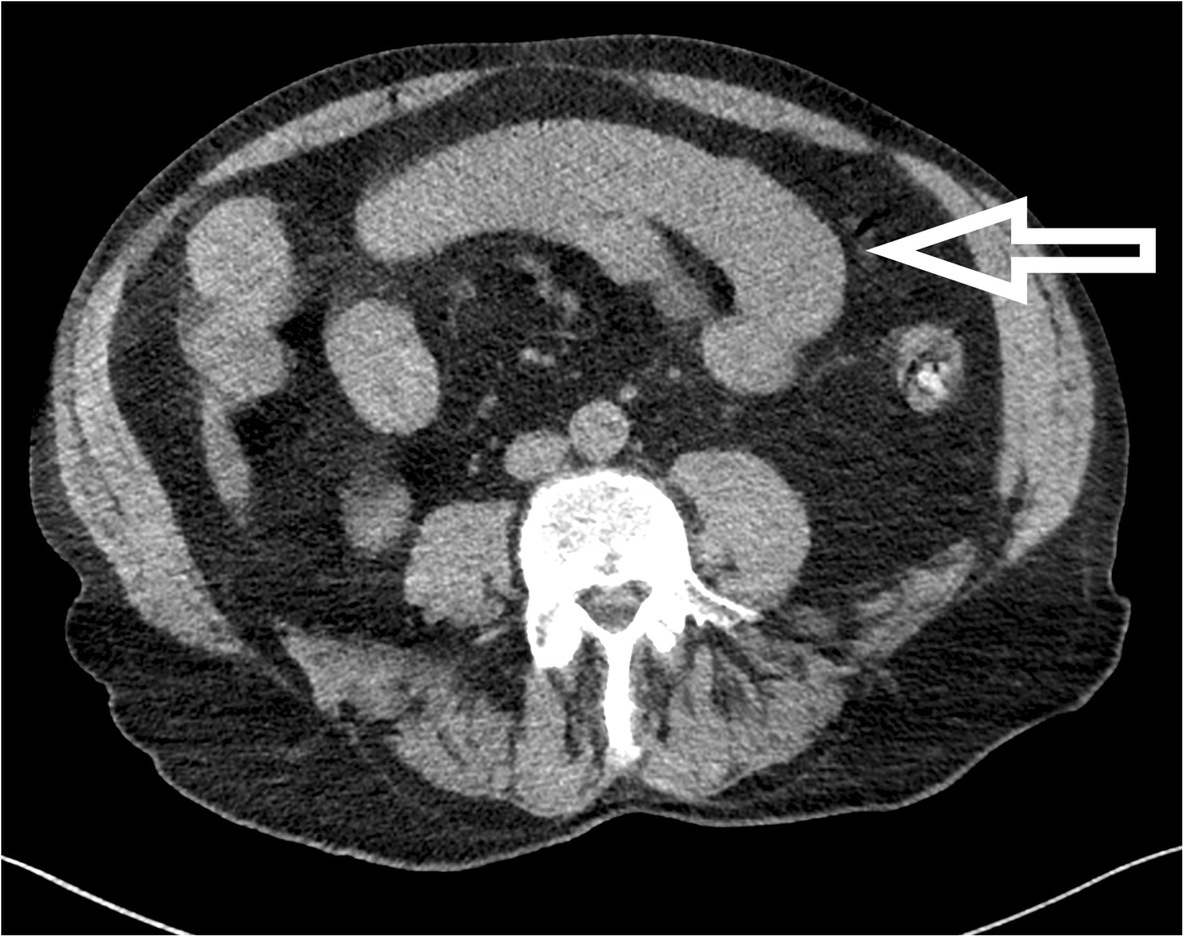

Fig. 3

From: Successful management of zinc phosphide poisoning—a Hungarian case

Abdominal CT-scan image of the patient on day 1. Native spiral-CT image of thorax, abdomen, and pelvis with soft tissue window and a 3-mm slice width in the axial plane. The thickened jejunal wall can be seen on the reconstructed image (marked with an arrow)